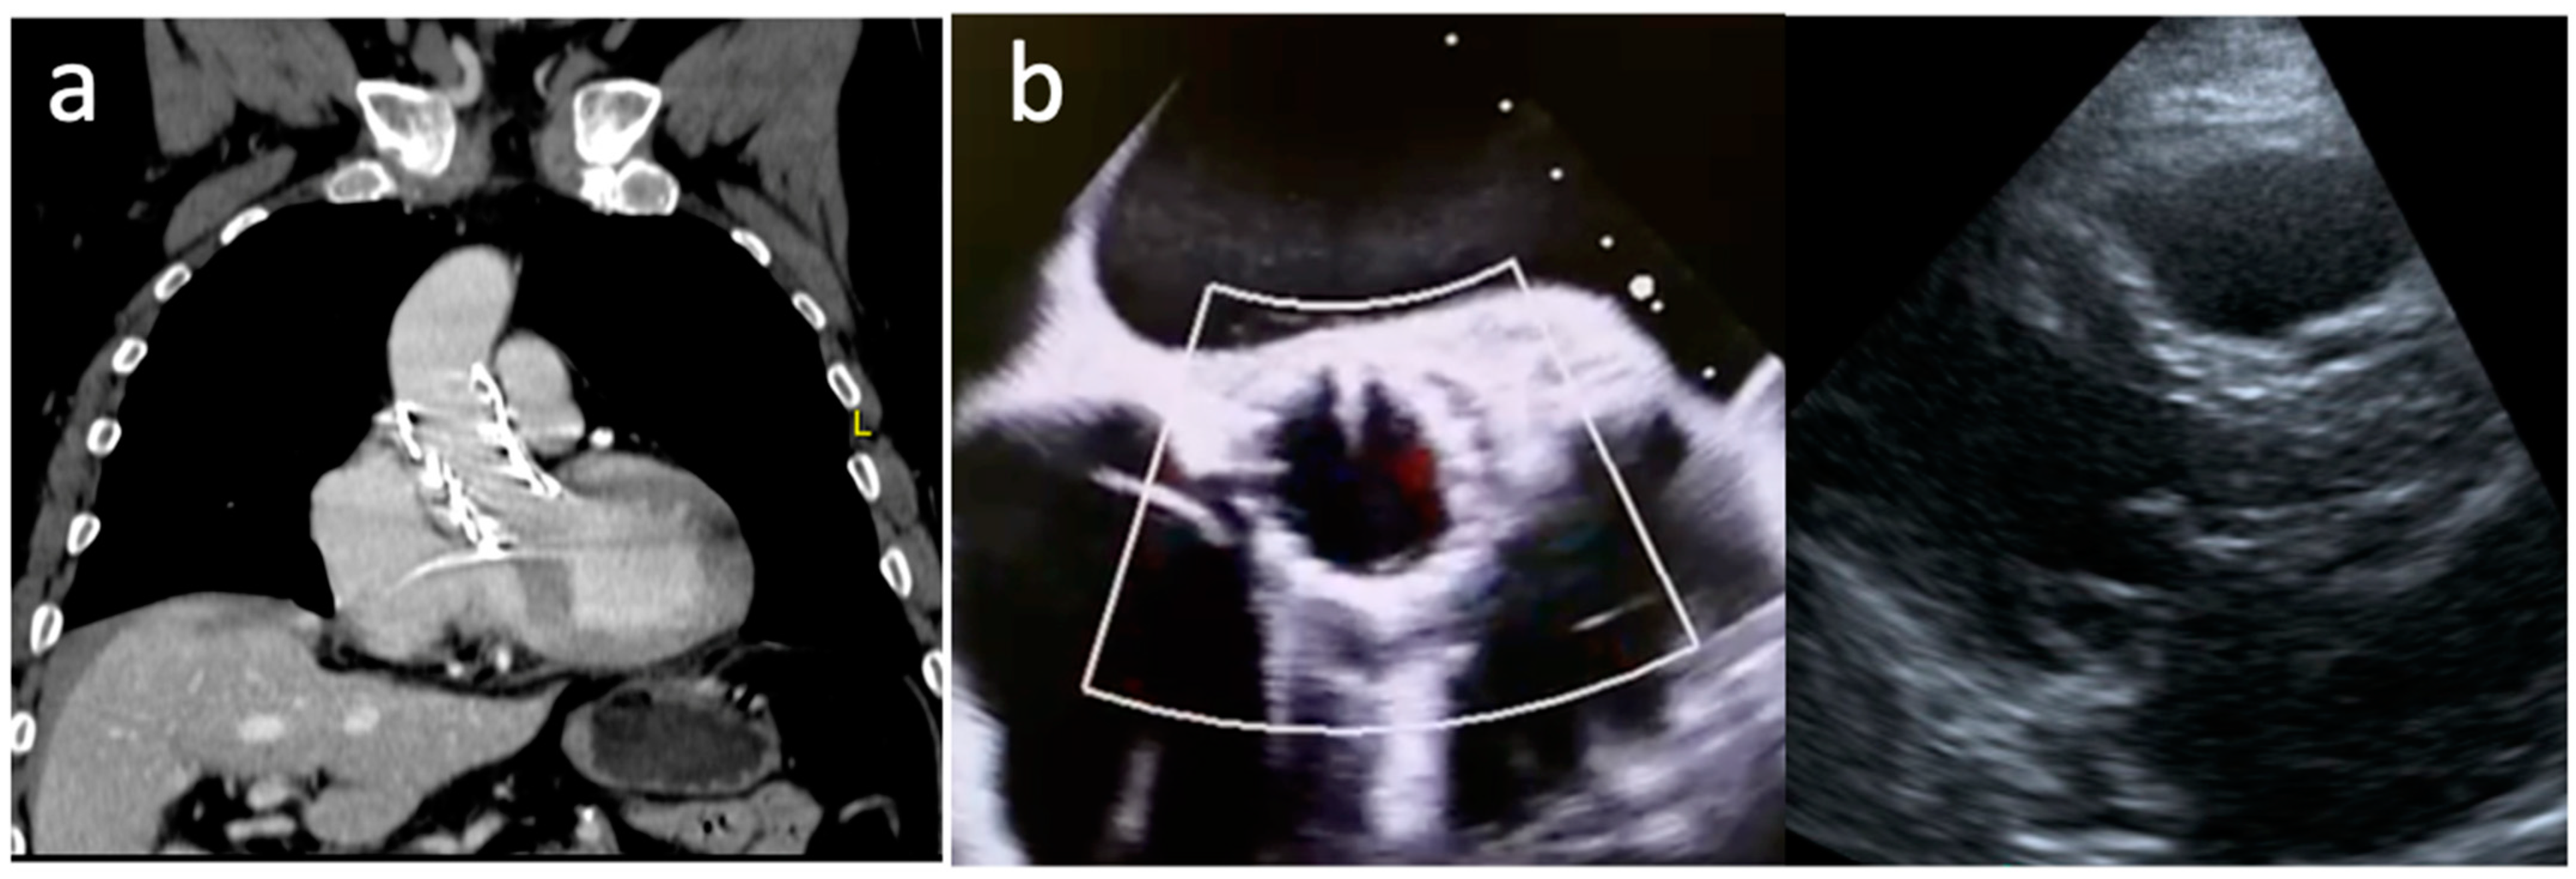

2. Clinical Vignette